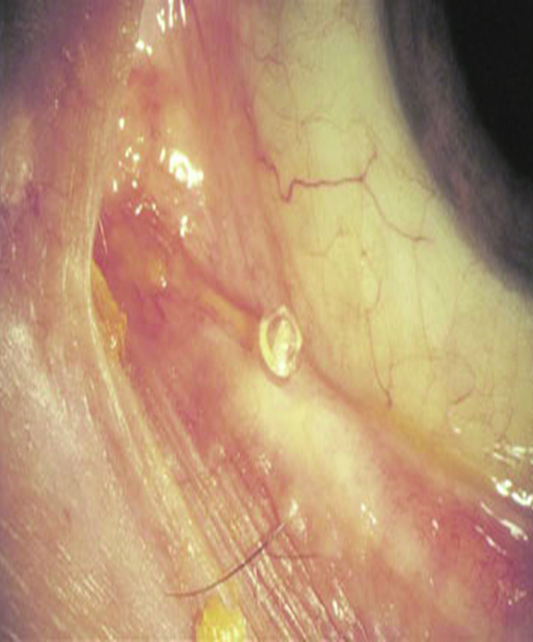

Con el rosa de bengala o la lisamina verde se puede determinar además el grado de fricción palpebral que se expresa al evertir el párpado superior y observar si el colorante tiñe el borde interno palpebral (Fig. 9).

Figura 9: Tinción con lisamina zona de fricción

En mi experiencia y opinión personal, sostengo hace largo tiempo que el uso de los denominados tapones lagrimales de silicona pueden agravar los cuadros inmunológicos y/o inflamatorios presentes en el ojo seco, al fomentar los fenómenos inmunocompentes por fricción sobre la superfcie ocular (Figs. 22, 23, 24).

Figura 22: Borde del tapón lagrimal sobre la superficie conjuntival y acúmulos secretorios secundarios.

Figura 23: Borde del tapón deteriorado friccionando la superficie ocular. Secreción, congestión y edema conjuntival.

Figura 24: Contacto del tapón lagrimal en conjuntiva.

Sostuve y sostengo también, que esa fricción crónica puede estimular a los linfocitos conjuntivales y en pacientes susceptibles desencadenar fenómenos de tipo linfoides.